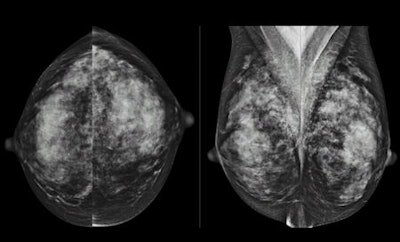

Speaking with AuntMinnie.com, Berg said looking for a cancer in women with dense breasts "is like looking for a polar bear in a snowstorm, where [the cancer] is hidden by the dense tissue. While digital mammography improves on that a little bit, it is still a problem even with the best mammograms. There is a lot of tissue that is the same whiteness as the cancer itself.... In fact, more than half of cancers in women with dense breasts will not be seen on mammograms."

Berg led a study in which a total of 2,809 women at 21 sites with dense breasts and at least one other risk factor for cancer agreed to have three annual independent screenings with mammography and ultrasound from April 2004 to February 2006. The median age at enrollment was 55 years, and approximately 54% of the women had a personal history of breast cancer.

Of the 2,662 women who underwent 7,473 mammogram and ultrasound screenings annually over three years, 110 of the subjects had 111 breast cancer events. Mammography detected 59 cancers (53%), including 33 (30%) cancers that were detected by mammography only.